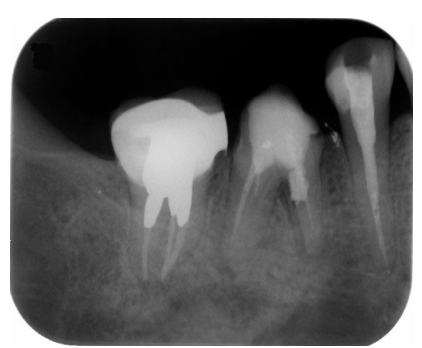

56. 如下圖,下顎右側第一大臼齒需拔除,第二大臼齒的頰側發現在靠近牙根分叉(furcation)處有 牙齦下蛀牙(subgingival caries),根據X光片中此牙齒與鄰牙的牙周狀況來評估,下列何種治 療計劃較適宜?

(A)根叉穿通術(tunnel preparation)後將蛀牙移除,然後製作牙橋 (B)將蛀牙移除並將牙齒分為兩半,然後製作牙橋 (C)拔除第一、二大臼齒後,以植體贋復重建 (D)頰側做牙冠增長術將蛀牙部分露出,移除蛀牙後製作牙橋